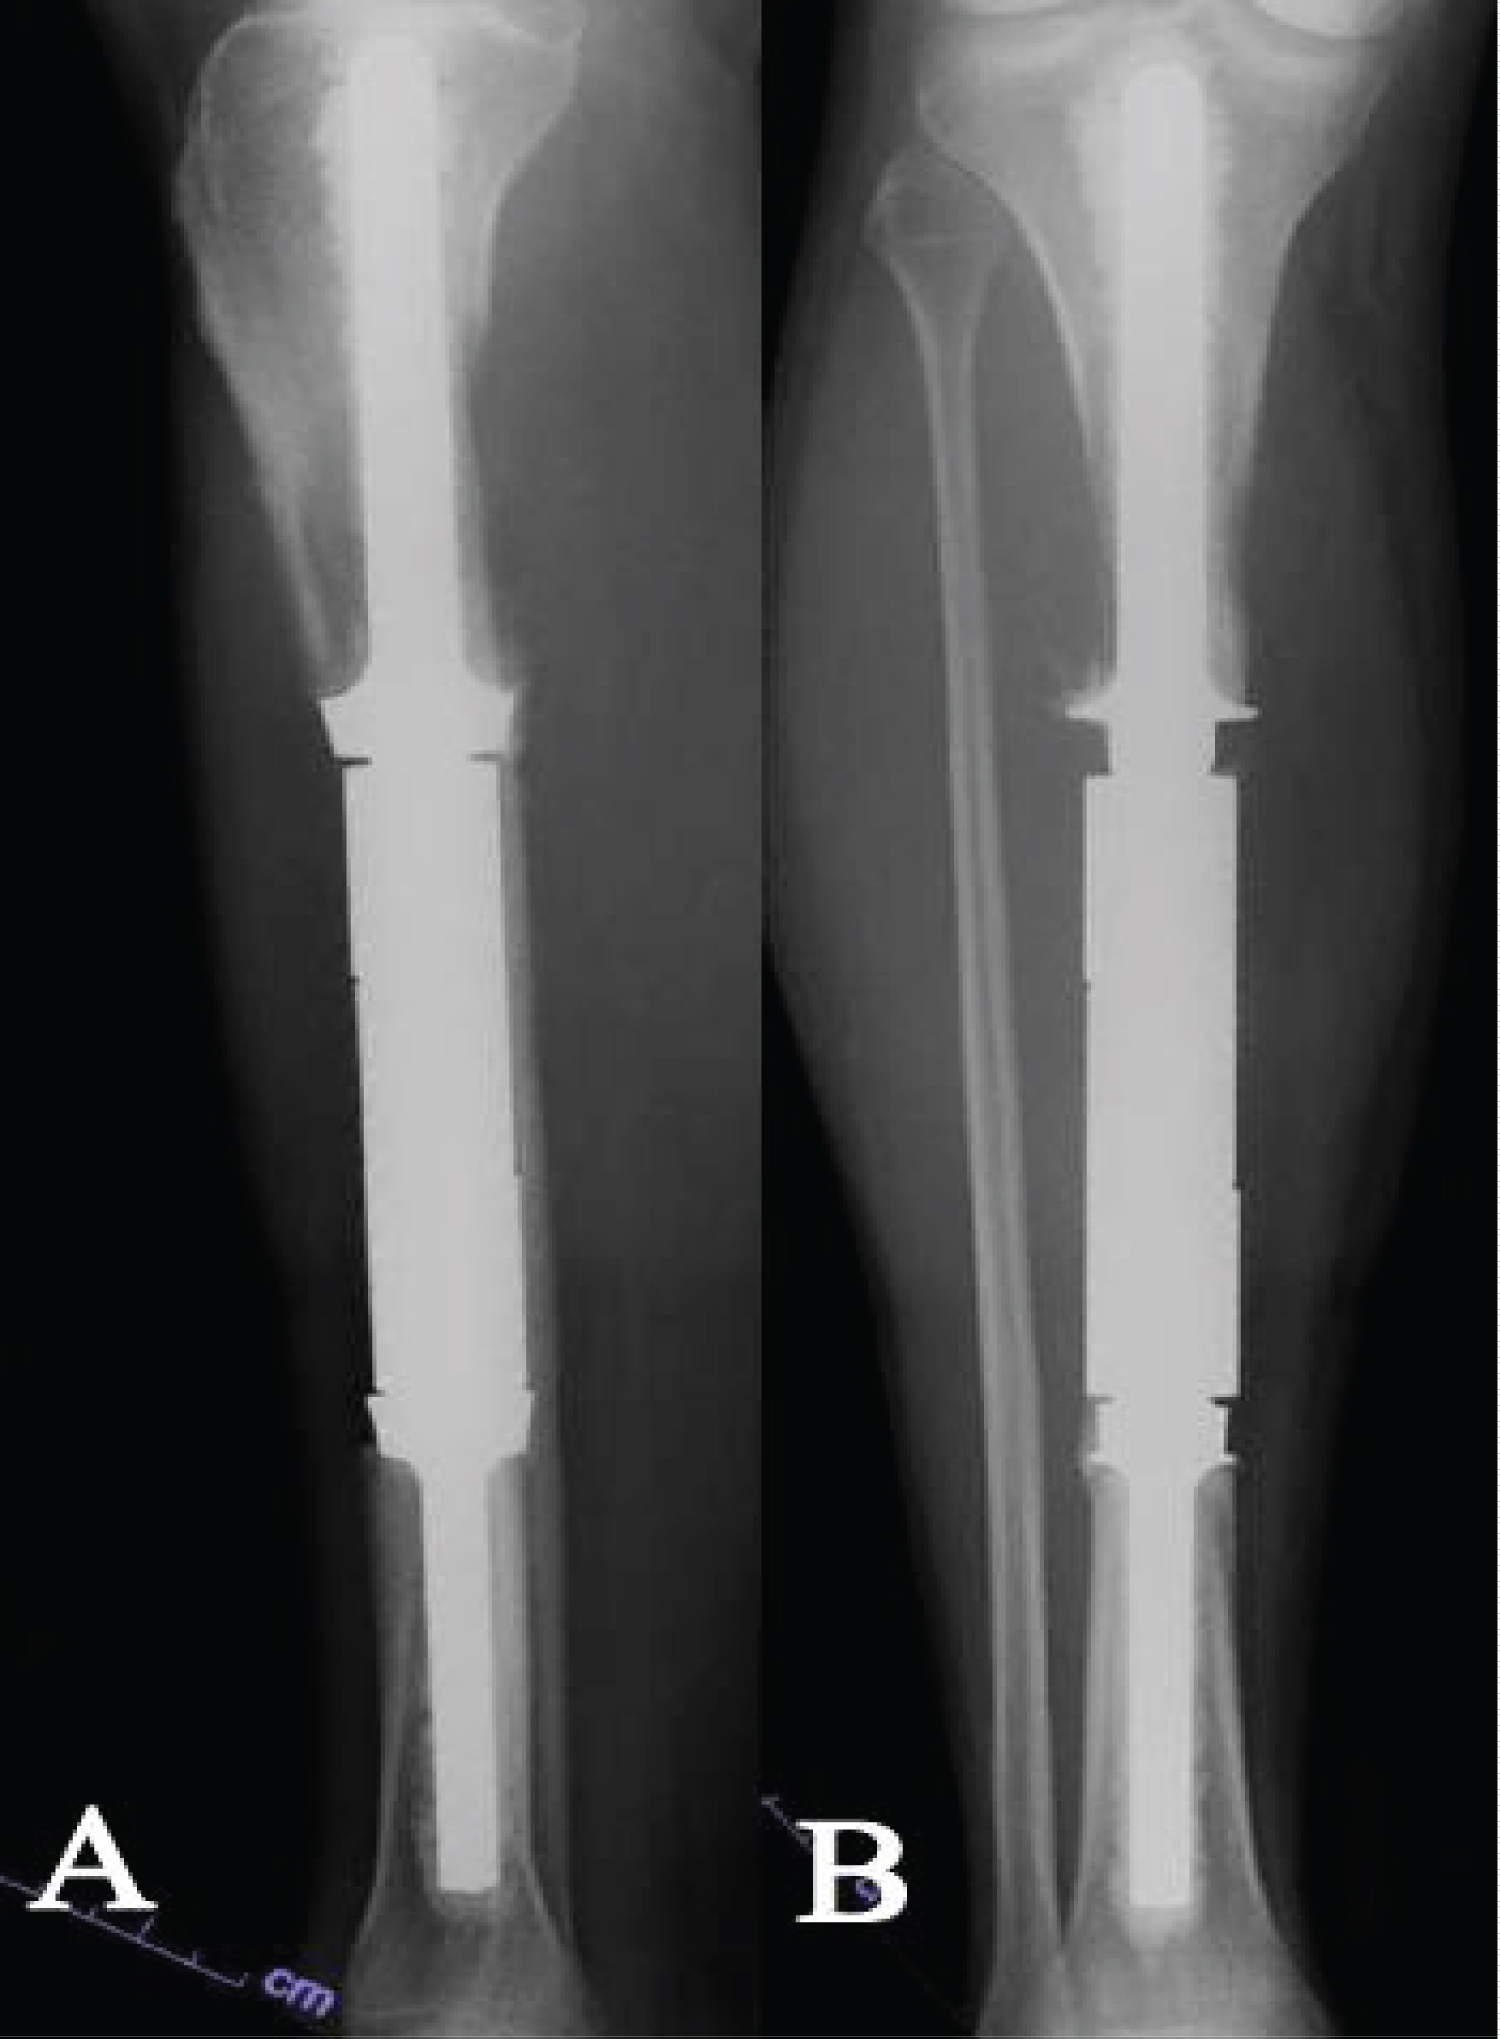

Figure 1: Anteroposterior (A) and lateral (B) radiographs of case 4 post-operatively. View Figure 1

We identified 12 patients who underwent limb salvage with intercalary endoprostheses. Three patients were excluded due to missing operative reports. An example of a tibial intercalary endoprosthetic reconstruction is shown in Figure 1. Patient demographics and implant data are listed in Table 1. The mean age was 46 years (29 to 76); six patients (66.6%) were male, and the average BMI was 28.7 kg/m 2 . The intercalary endoprostheses included three femoral prostheses, three tibial prostheses, and three knee spanning arthrodeses. The mean follow up was 52 months (0 to 188).